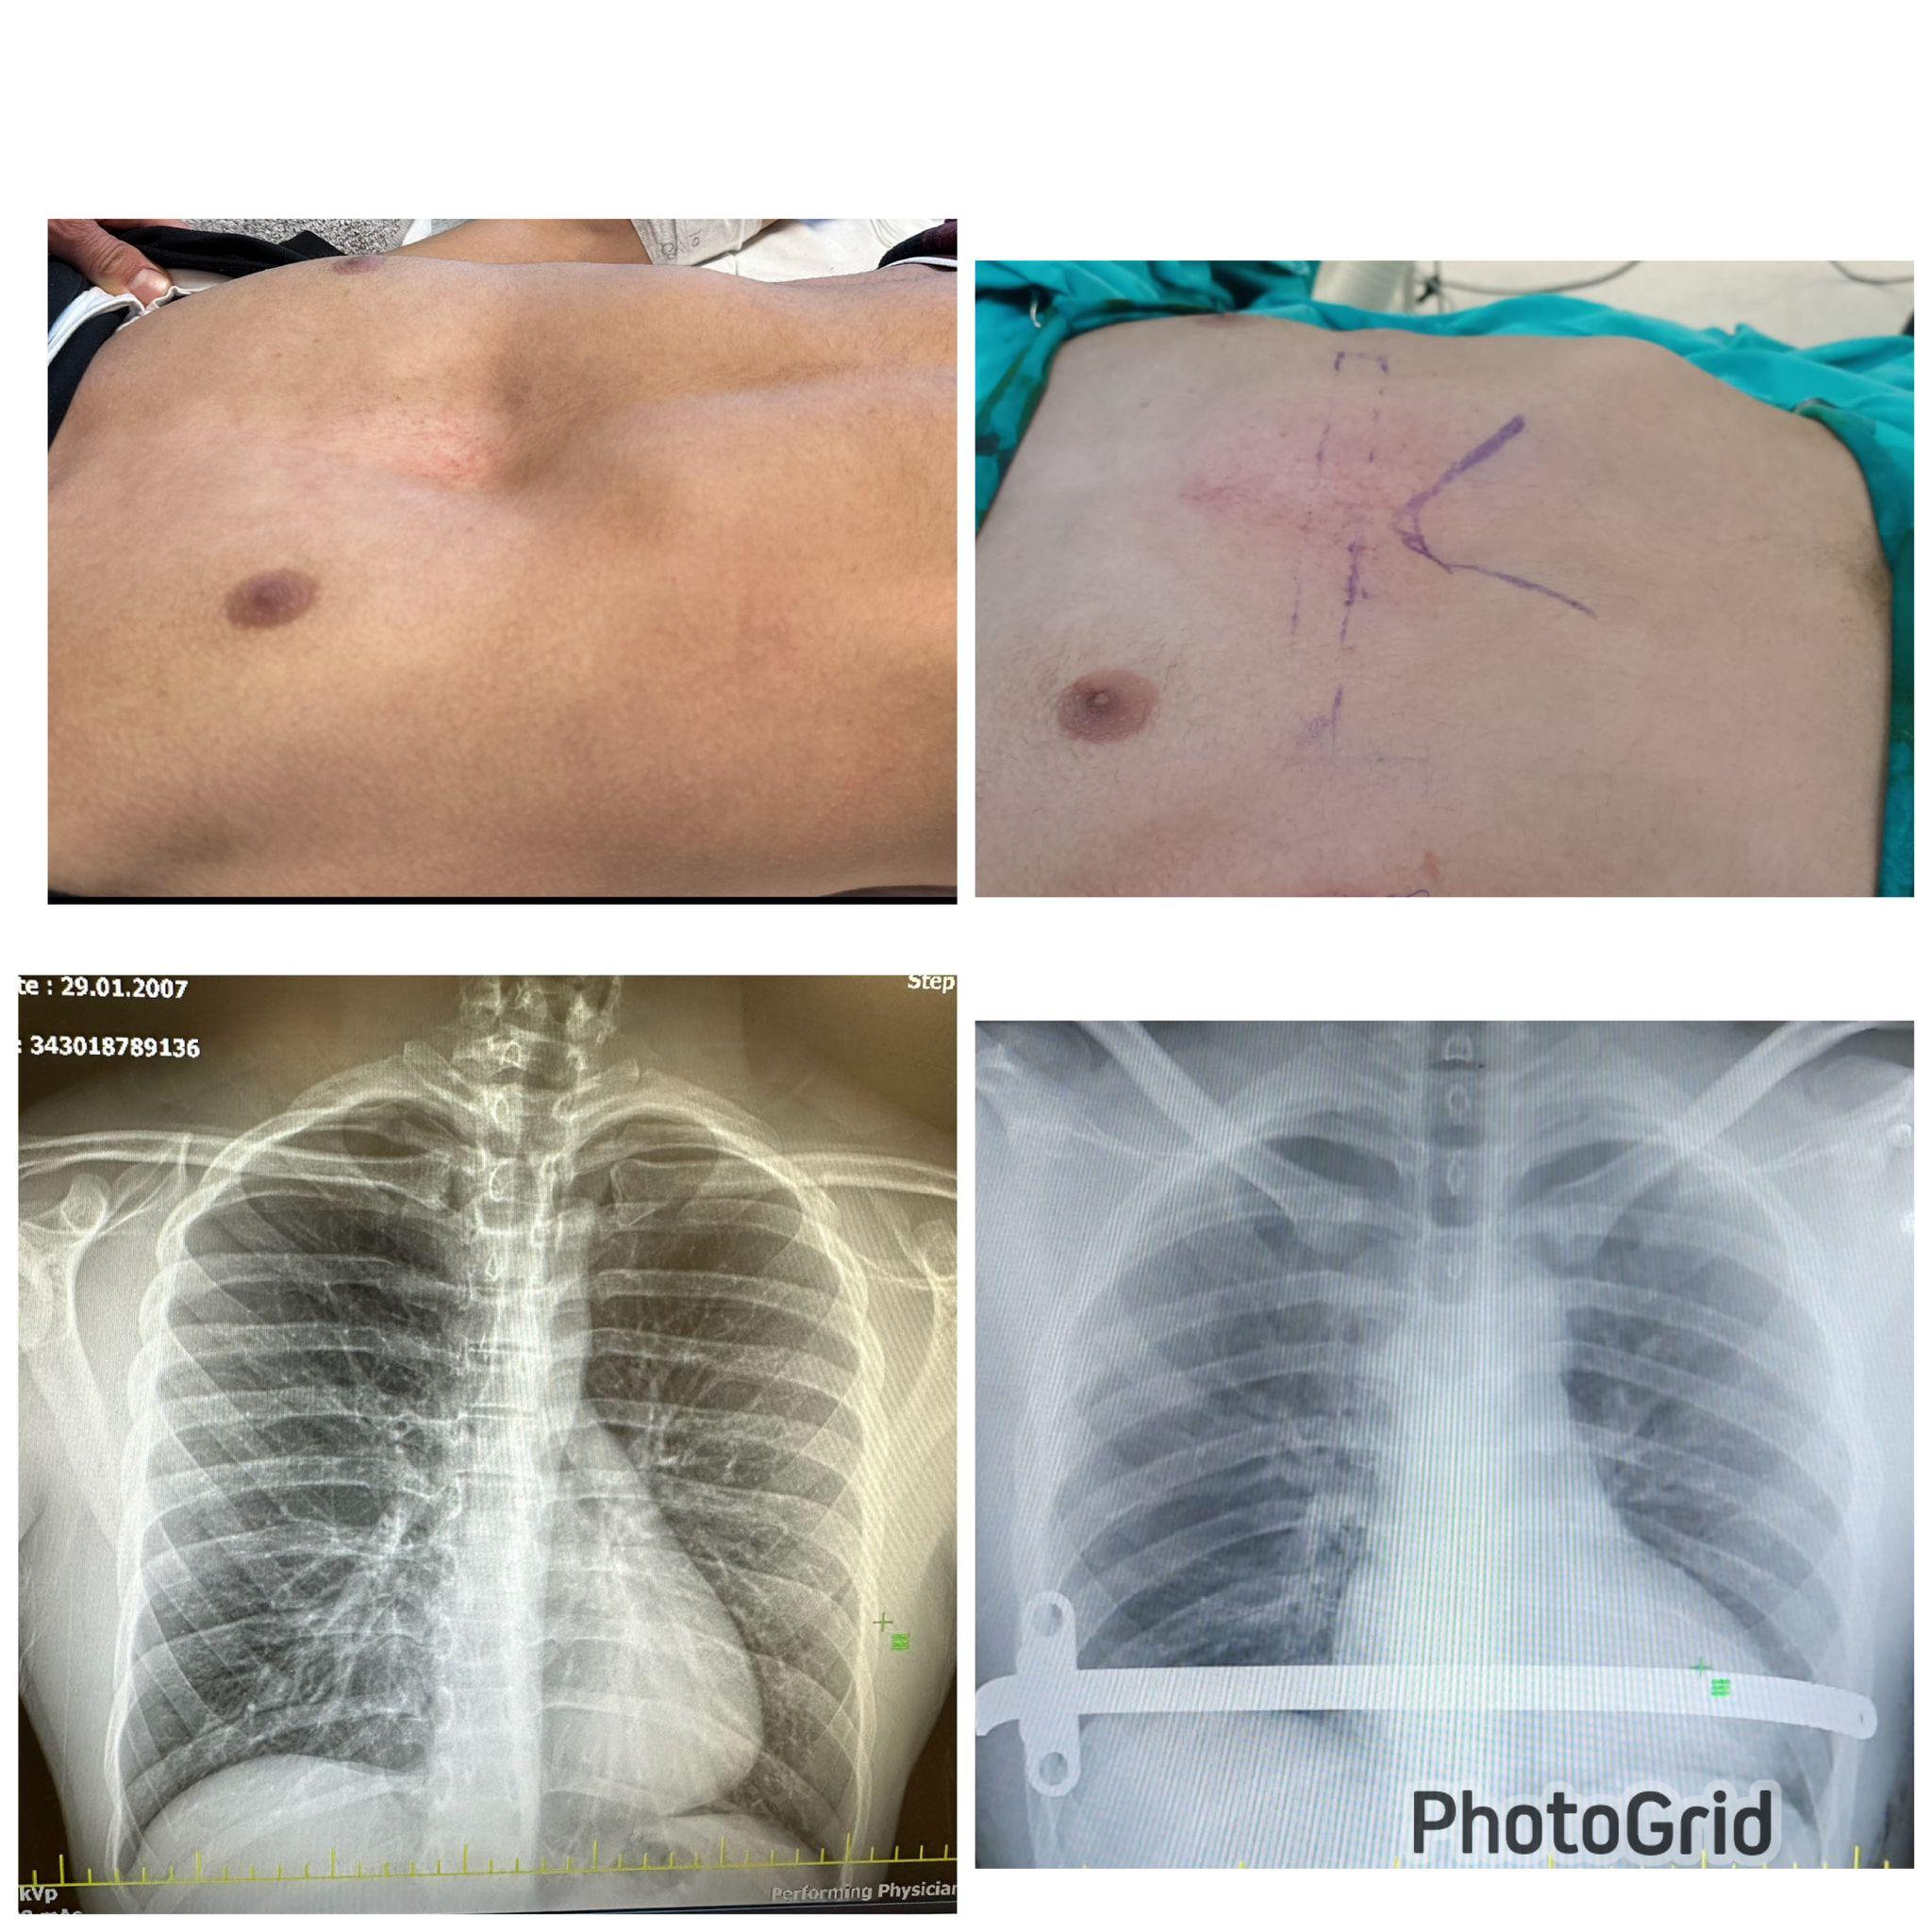

tek barla kunduracı göğsü düzeltilmesi